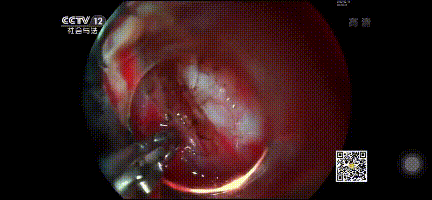

恰逢安瑞助力的央視頻道CCTV.12首播《胃鏡下早癌切除術》,正是學習手術操作和深度了解啄木鳥刀、鷹夾、止血鉗等手術耗材時。

經胃鏡檢查,胃底黏膜近賁門處有黏膜下腫物,大小約0.8cm。取病理診斷,疑似間質瘤。擬行手術:胃鏡下早癌切除術。

安瑞啄木鳥刀通過胃鏡進入,I刀環繞腫瘤通電標記,標記完成,I刀/O刀逐層剝離肌瘤。

安瑞止血鉗正給腫瘤旁血管快速止血,保持術野干凈,繼續剝離瘤體。